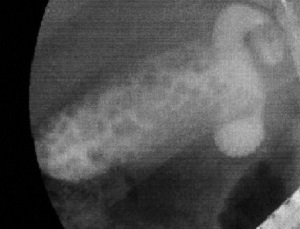

帰宅する頃には、当然みぞおちの痛みが最高潮に達した。この日はほぼ一睡もできずにそのまま出社するハメになったが、朝のトイレでは仰天した。おしっこの色がまるでウーロン茶のようにまっ茶色だったのだ。さすがにこれはマズかろうと、出社前に病院に寄って薬をもらったものの、痛みは収まらず、結局夕方には帰宅。そのまま痛みが落ち着くこともなく、早朝になって救急指定病院に駆け込む事態に。そこで初めて受けたエコー検査によって、ようやく胆のう内に大量の石、つまり胆石が詰まっていることが明らかとなったのだった。

エコー検査の写真。医者からもらう。左側のボツボツが詰まった胆石